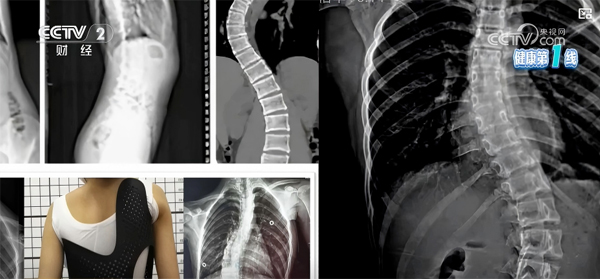

脊柱侧凸是一种复杂的脊柱三维畸形,国际脊柱侧凸研究学会(SRS)明确将其定义为:在站立位全脊柱冠状面X线片测量Cobb角≥10°。其中,特发性脊柱侧凸病因尚不明确,约占脊柱侧凸

脊柱侧凸是一种复杂的脊柱三维畸形,国际脊柱侧凸研究学会(SRS)明确将其定义为:在站立位全脊柱冠状面X线片测量Cobb角≥10°。其中,特发性脊柱侧凸病因尚不明确,约占脊柱侧凸发病率的80%,而青少年特发性脊柱侧凸(AIS)是最常见的类型,发生于10~18岁青少年群体。

矫形支具是国际公认的控制脊柱侧弯进展最有效的非手术手段之一,适用于Cobb角超过20°且进行性加重风险较大的中重度脊柱侧弯患者,可单独应用,若同时配合专项康复训练,矫正效果会更佳。根据材质、矫正原理的不同,临床常用支具分为硬支具和软支具两类。